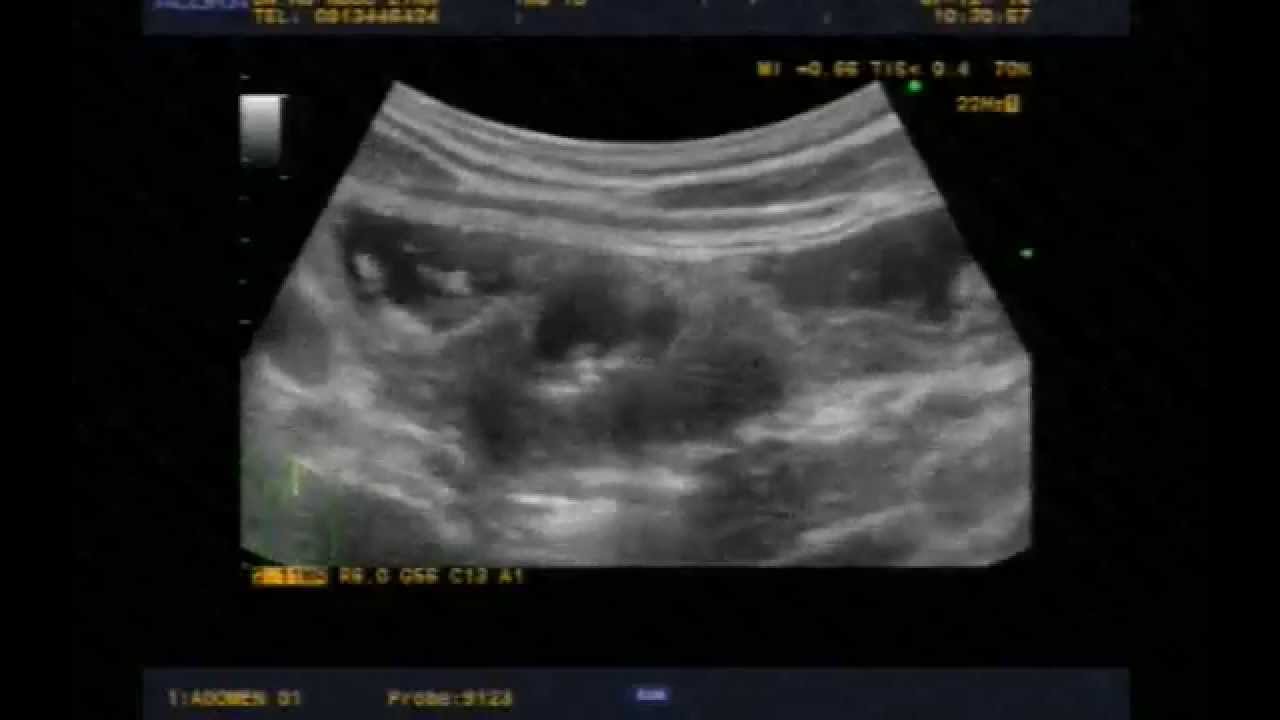

Ako me pošalju kući, da li ću imati primanja do kraja ... from www.inozemstvo-posao.com Loss of or decrease in appetite. Stomach cancer, also known as gastric cancer, is a disease that occurs when uncontrolled growth of the cells that make up the inner lining of the stomach walls leads to the formation of tumors. Blood in vomit or stool. Image if you have stomach cancer within what does stomach cancer feel like article related to what does stomach cancer feel like : When stomach cancer does cause signs and symptoms, they can include: Sometimes there are no signs or symptoms of stomach cancer or duodenal or gastric ulcers, and when they do occur, they may include nausea and loss of appetite with no clear cause. Sometimes, people with stomach cancer do not have any of these changes. Rarely, there is blood in the vomit.

Stomach cancer is difficult to treat because it's often already advanced by the time it's diagnosed. When death is very near, you might notice some physical changes such as changes in breathing, loss of bladder and bowel control and unconsciousness. But for many sufferers, pain is not among the early warning signs of stomach cancer. Your stomach receives and holds the food you eat and then helps to break down and digest it. It makes sense that a cancer growing in your stomach could make you feel bloated, or mess with your bowel movements. When palliative care is used along with all of the other appropriate treatments, people with cancer may feel better and live longer. So when stomach cancer spreads to the liver (or any other part of the body), it's still called stomach cancer. Stomach cancer, or gastric cancer, is a fairly uncommon type of cancer. It's not called liver cancer unless it starts from cells in the liver. The stomach is a muscular sac located in the upper middle of your abdomen, just below your ribs. Medical organizations don't recommend routine screenings for most people, as is the case with other types of cancer such as breast or colon cancer. To doctors, the cancer cells in the new place look just like the ones from the stomach. Image if you have stomach cancer within what does stomach cancer feel like article related to what does stomach cancer feel like :